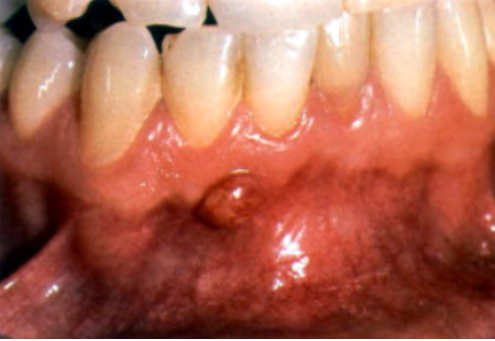

What is this clinical finding?

A parulis

It is not a pyogenic granuloma

A parulis is a proliferation of granulation tissue at the opening of a sinus tract

When the infection breaks through the alveolar bone and presents itself,

it will sometimes cause this proliferation of granulation tissue